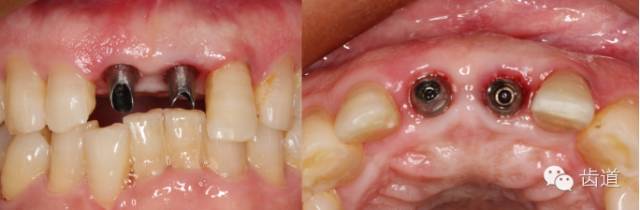

植入種植體(唇側(cè)留2-3mm jumping gap)

確定植入深度(齦下3-4mm)

小直徑愈合基臺(tái)就位后唇側(cè)植骨

更換大直徑愈合基臺(tái)

本病例為前牙外傷致根折,牙周無(wú)明顯炎癥,唇側(cè)骨板厚度大于1mm且根方骨量充足,適合即刻種植。術(shù)前簡(jiǎn)易導(dǎo)板的制作以及術(shù)中牙周探針精確的測(cè)量,保證了種植體的三維位置及軸向均按標(biāo)準(zhǔn)的即刻種植手術(shù)進(jìn)行。術(shù)后參考拔除牙齒的頸部形態(tài)制作個(gè)性化愈合基臺(tái),實(shí)現(xiàn)了對(duì)牙齦塑型的早期干預(yù),打破了傳統(tǒng)二期牙齦成型的做法,所成型的牙齦袖口與之前的天然牙相似,有利于維持牙齦形態(tài)的穩(wěn)定和美觀。